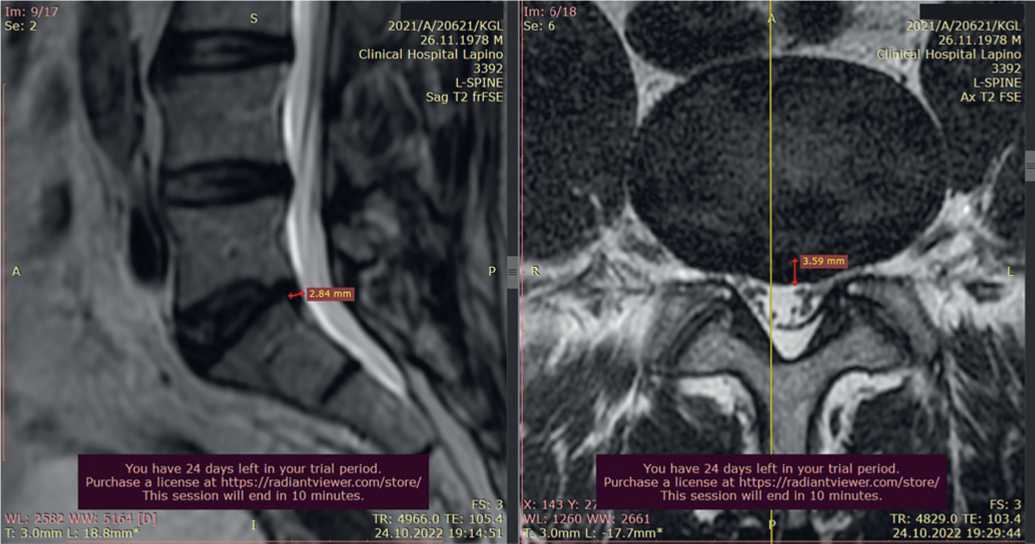

Пациент И., 41 года, обратился в Центр китайской медицины «Синь-я-Чжу» 09.09.2020 с жалобами на постоянную тянущую боль в пояснице с иррадиацией в левую нижнюю конечность. Резкий болевой синдром пациент отмечал даже при легком наклоне вперед, при попытке встать со стула и при ходьбе.

При МРТ от 09.09.2020 обнаружена грыжа диска L5–S1 размером 6,2 мм, отечность окружающих тканей (рис. 6).

Рис. 6. Исходная магнитно-резонансная томограмма пациента И. при обращении 09.09.2020: A) саггитальные срезы, B) аксиальные срезы на уровне межпозвонкового диска L5–S1

Fig. 6. Initial magnetic resonance imaging of patient I. upon presentation on 09.09.2020: A) sagittal sections, B) axial sections at the level of the intervertebral disc L5–S1

После курса акупунктуры болевой синдром купирован. При контрольной МРТ от 28.12.2020 отмечено уменьшение грыжевого выпячивания до 5,3 мм (рис. 7).

Рис. 7. Контрольная магнитно-резонансная томограмма пациента И. после курса акупунктуры 28.12.2020: A) саггитальный срез, B) аксиальный срез на уровне межпозвонкового диска L5-S1

Fig. 7. Control magnetic resonance imaging of patient I. after acupuncture course on 28.12.2020: A) saggital slice, B) axial slice at the level of intervertebral disc L5-S1